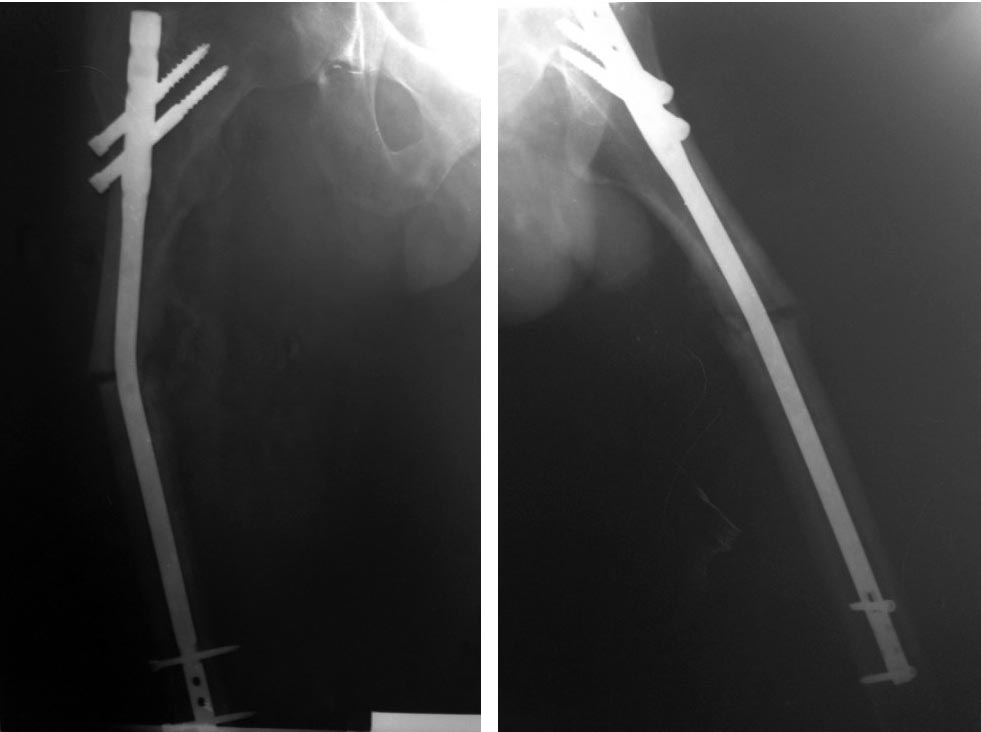

Пациент- мужчина, 25 лет, травма в ДТП 26.03.2016г., прооперирован по поводу перелома бедра 11.04.2016г.- закрытая репозиция, БИОС стержнем ChM 10 мм,L 320 мм. В результате повторной травмы 13.07.2016г.стержень согнулся во фронтальной плоскости под углом 20 гр.Как удалить? Менять способ фиксации или повторно БИОС?

Должно удалиться скользящим молотком без проблем, угол небольшой, стержень тонкий. Дальше - рассверлить до 14 мм, и заштифтовать стрежнем 12 мм. А зачем там рекон был использован?

Можно удалить стандартнымспособом. А дальше - рссверливание и замена стержня. Рассверливание максимально до 12 мм - стержень 11,5 мм а дальше в такой пропорции.

Мне кажется, или шейка бедра сломана? уточните по МСКТ

Мне кажется стержень может не пойти с таким углом деформации. Можно попробовать его выгнуть обратно на операционном столе, но есть реальный риск сделать хуже. Или пойти на высоту деформации стержня оттрепанировать кость ( немного), перепилить стержень, и удалить дистальный из места перелома, проксимальный из места постановки.